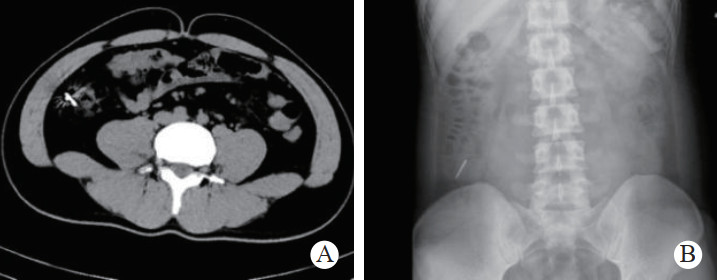

1 一般资料患者,男性,32岁,职员,因“误吞金属钉状物7 d”就诊。患者7 d前误吞入金属钉状物一根(大小约3 cm),患者无明显不适症状,未诊治。4 d前出现下腹隐痛,行急诊全腹CT检查,见图 1,行急诊胃镜检查未见明显异物。后复查腹部CT示异物进入小肠内(图 2),普外科会诊建议随访。2 d前复查腹部CT(图 3),继续保守治疗。1 d前患者为行异物取出入院,复查腹部CT可见异物至结肠内(图 4)。急诊予以聚乙二醇电解质散导泻清肠,行无痛肠镜下异物取出术。本文已通过本院伦理委员会审批,伦理审批号为:(2021)伦审研第(0252)号,并通过免除知情同意申请。完善术前检查,进行药物导泻清肠时,关注患者有无腹痛等现象,以免因服用药物清肠,肠蠕动加快,尖锐异物在消化道内随蠕动前行,尖端嵌插在肠壁中而停滞不前,并随着后方内容物的推进,加深尖锐异物刺入肠壁,最终导致穿孔及出血的发生。本例患者安置在独立单人间进行肠道准备,不定时进行腹部查体及观察排泄物的性状,早期发现穿孔、出血指征,以便尽早进行外科手术干预。与此同时,内镜中心医护人员联合外科、放射科、麻醉科医生制定诊疗方案,若发生此类情况,立即予急诊行腹部X线或CT检查,一旦确定出现穿孔或出血等情况,即刻行急诊手术治疗。

| 图 2 腹部CT示小肠内条索状致密影,周边放射状明显,邻近肠系膜未见渗出和积气 |

| 图 3 腹部CT示升结肠起始部管腔内致密影,约3.2 cm, 周边放射状明显,邻近肠系膜未见渗出和积气 |

| 图 4 腹部CT示回盲部致密影,提示异物 |